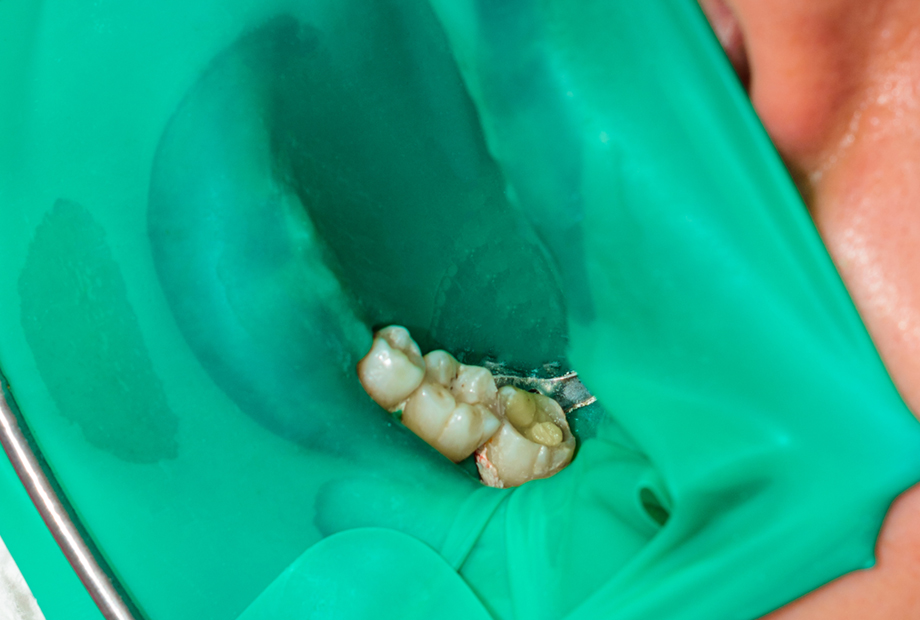

最新のマイクロスコープやCTでより確実に歯の状況が見えるようになりましたが、根管治療に大事なのはそれだけではありません。「治療中の歯に菌を入れない」「できうる限りの無菌環境で治療を行う」ことが非常に重要です。そのために精密根管治療ではラバーダムという、歯にゴムシートを使用し、口内と治療中の歯の隔離作業が必要です。

ラバーダムは治療する歯を守り、器具や薬品が患者様の口内にこぼれたりすることも防いでくれるため、安全な治療のためには重要な治療法です。